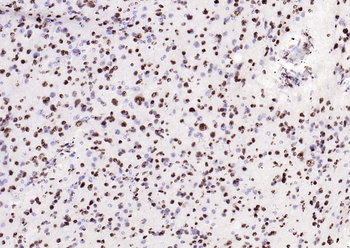

Phospho-Smad3 (Ser423 + Ser425) Rabbit Polyclonal Antibody [orb6983]

FC, IF, IHC-Fr, IHC-P, WB

Bovine, Canine, Equine, Gallus

Human, Mouse, Porcine, Rat

Rabbit

Polyclonal

Unconjugated

100 μl, 200 μl, 50 μlPhospho-SMAD5 (Ser463 + Ser465) Recombinant Rabbit Monoclonal Antibody [orb559123]